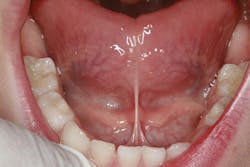

That was not the end of his treatment, though. My son still had a tight lingual frenum, which limited his ability to place his tongue on the roof of his mouth during rest. This resulted in underdeveloped arches and less room for the tongue. He also still had some trouble saying certain letter sounds, such as "L," "6," and "R."

Example of a tight lingual frenum restricting movement of the tongue:

The treatment for these symptoms included myofunctional therapy and a lingual frenulectomy. A myofunctional therapist is typically a speech pathologist or hygienist who has undergone additional training to help correct issues related to mouth breathing, tongue posture, and tongue habits. A listing of myofunctional therapists can be found at www.myoacademy.net, which is the website for the Academy of Orofacial Myofunctional Therapy. There seem to be a lack of trained myofunctional therapists - we need more!

We started my son on some myofunctional exercises to help strengthen and stretch his tongue prior to the frenulectomy. We then used a laser to release the frenum. Oftentimes this needs to extend deep into the fibrous tissue in order to get the necessary functional benefit. Due to the highly vascular nature of the tongue, this is a procedure to be careful with. Directly after the release of his frenum, we did some stretching exercises to help ensure the frenum did not reattach. Again, the degree of tongue-tie can vary. A posteriorly tight frenum can present problems and requires a more technique-sensitive frenulectomy.